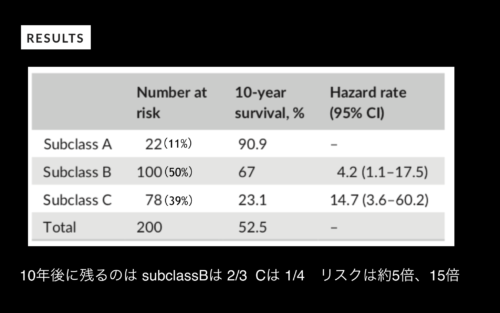

今回のテーマは、奥歯の歯周病で、特に分岐部病変と言われるものでした。

経過観察するにしても、どれくらいの生存率なのか、というところも勉強になりました。